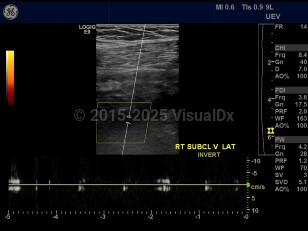

Subclavian vein thrombosisSubclavian vein thrombosis